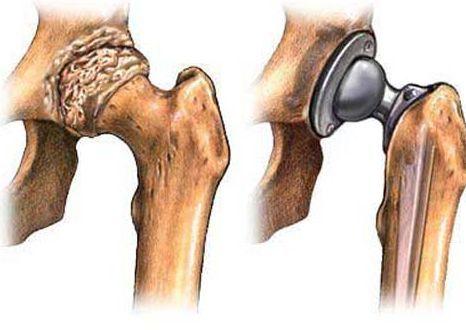

5、外科手术

如果保守治疗不起作用,你可能需要考虑骨头重整、关节置换的手术了,一般来讲,外科手术的风险包括感染和血栓。另外,人工关节也可能会磨损或脱落,最终可能需要更换。